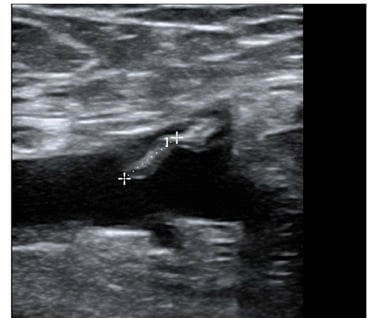

Endovenous glue ablation for lower limb varicose veins is gaining traction due to its proven safety and efficacy. A significant concern, however, is the extension of glue-associated thrombus into deep veins. This article presents a case where thrombus extended into the common femoral vein post endovenous glue ablation for varicose veins using the VenaSeal™ closure system (VCS; Medtronic). A 63-year-old male, presenting with symptomatic varicose veins and saphenofemoral junction incompetence, underwent the VCS closure. A month later, while varicosities showed improvement, an ultrasound revealed thrombus extending into the common femoral vein. This was managed with surveillance duplex and serial clinical observation, showing spontaneous resolution at 12 months. As the use of VCS for varicose veins increases, it's anticipated that thrombotic complications in the deep veins will be encountered more frequently, necessitating the formulation of guideline-based management for this complication.